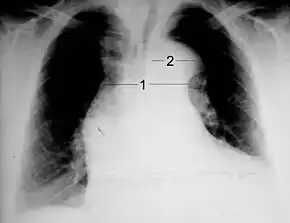

Chest X-ray

Chest radiography may demonstrate a change in shape of the thoracic aorta. Classically, new widening of the mediastinum is of moderate sensitivity for detecting an ascending aortic dissection; however, this finding is of low specificity, as many other conditions can cause apparent widening of the mediastinum.

There are several other associated radiographic findings:

- The "calcium sign" describes an apparent separation of the intimal calcification from the outer aortic margin by greater than 10 mm.

- Pleural effusions, more commonly in descending aortic dissections, and typically left sided.

- Other: obliteration of the aortic knob, depression of the left mainstem bronchus, loss of the paratracheal stripe, and tracheal deviation.

Importantly, about 12 to 20% of aortic dissections are not detectable by chest radiograph; therefore, a "normal" chest radiograph does not rule out the condition. If there is high suspicion, a more sensitive imaging test (CT angiogram, MR angiography, or transesophageal echo) may be warranted.